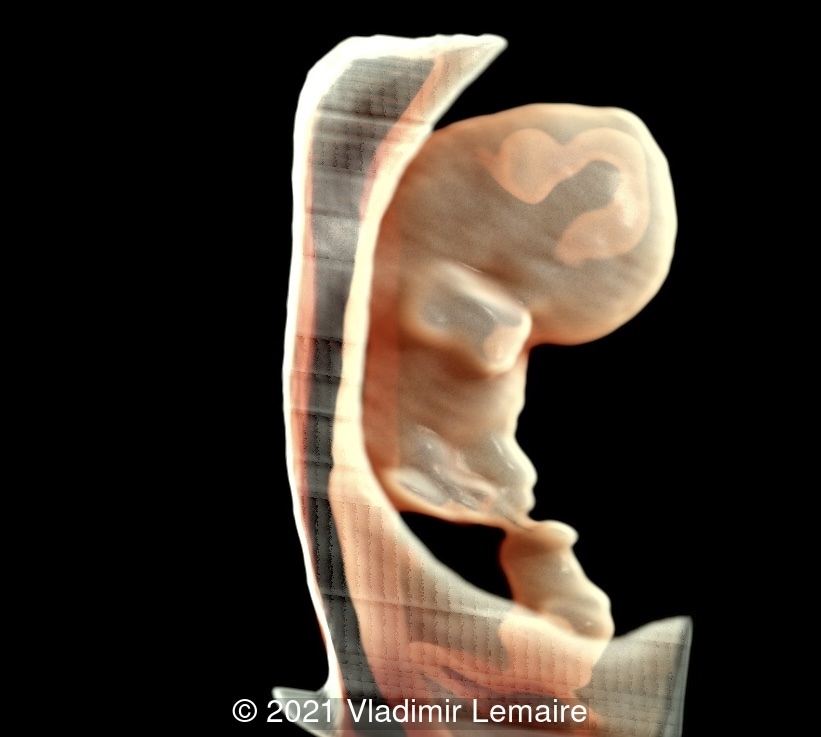

Image obtained by augmenting the transparency effect and adjusting light effects.

Image 4 Image obtained by augmenting the transparency effect and adjusting light effects.